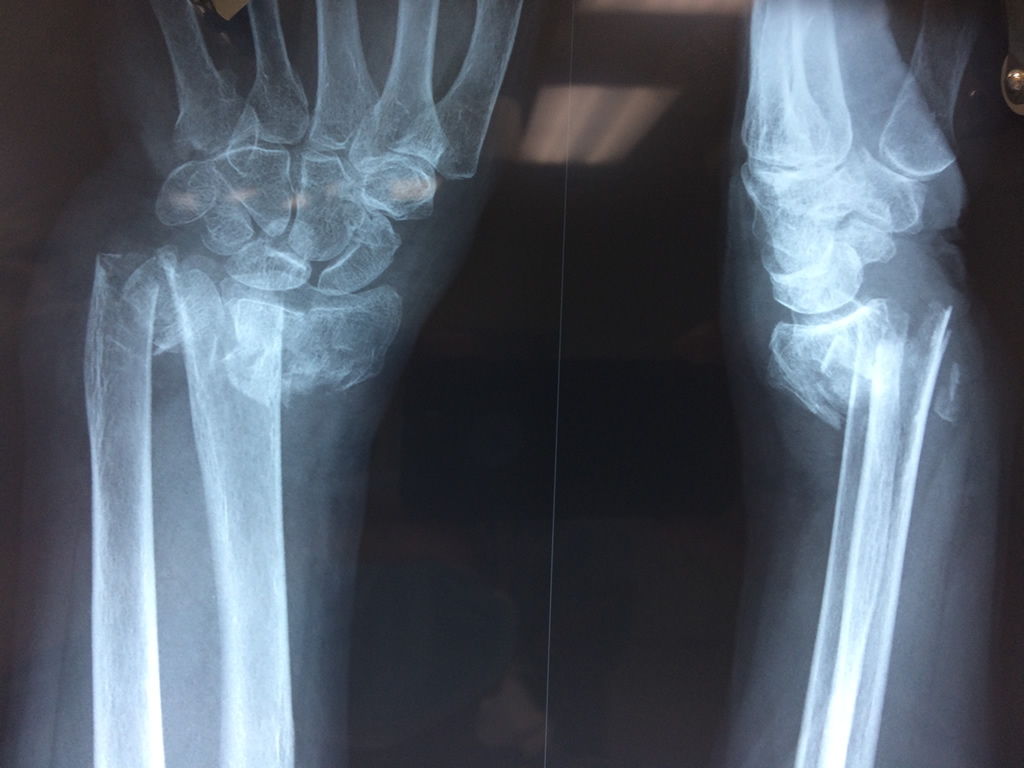

Cirugías de Muñecas

Los procedimientos más comunes en cirugía de la mano son aquellos destinados a reparar traumatismos, incluyendo lesiones de tendones, nervios, vasos sanguíneos, y articulaciones; huesos fracturados; y quemaduras, cortes, y otros daños de la piel.